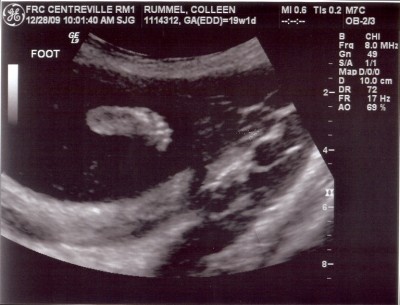

So cute! I love sonogram pics.